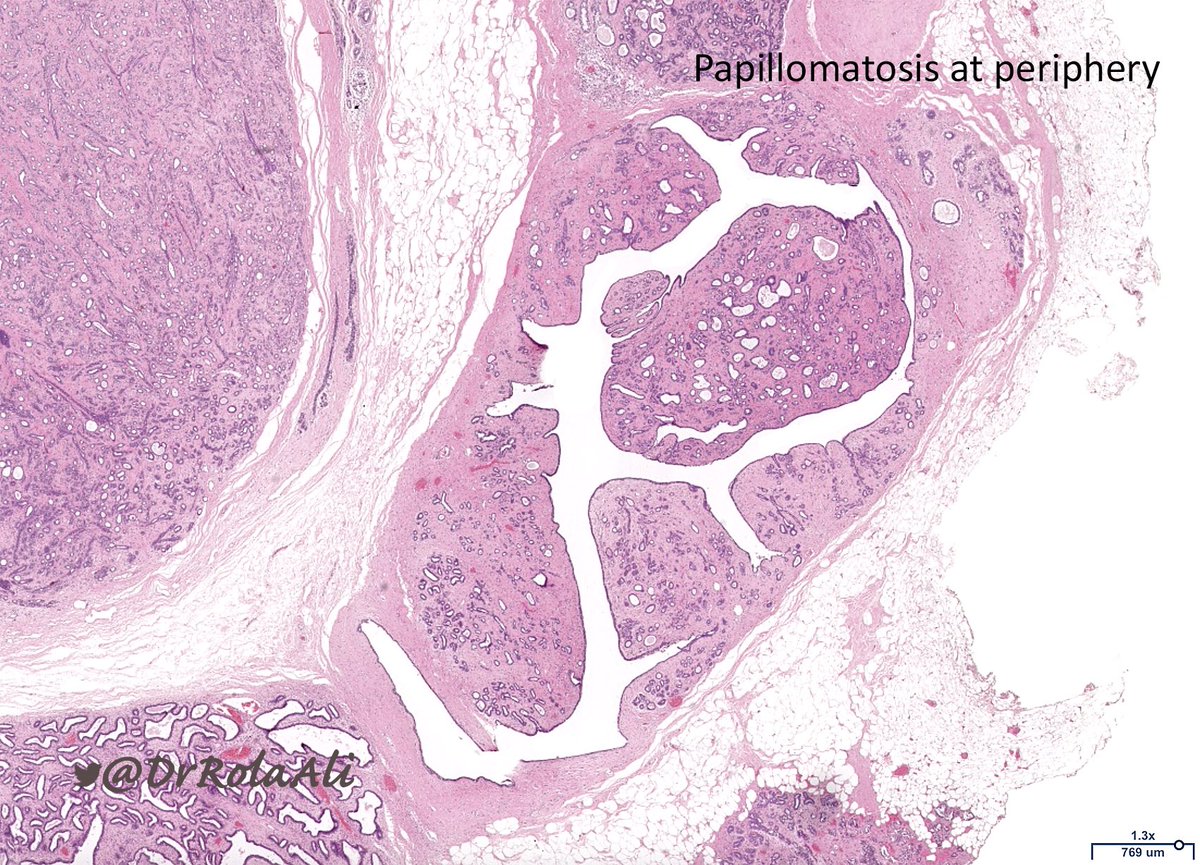

🔬 Adenomyoepithelioma

▪️Typically multinodular

▪️Biphasic

▪️Myoepithelial cells may be: polygonal and clear, spindle, myoid, plasmacytoid

▪️+/- accompanied by papillomatosis

▪️Benign